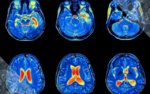

ЛСД и сканирование мозга.

В апреле 2016 года исследователи опубликовали первые современные снимки сканированного мозга людей, находящихся под воздействием ЛСД. Обосновавшаяся в Великобритании команда учёных выяснила, что лизергиновая кислота снижает активность в некоторых мозговых областях, при этом усиливая связь между ними.

20 добровольцам ввели высокие дозы ЛСД и сканировали их мозг на протяжении шести часов. Мозг "сидящих" на психоделическом препарате не отличался от мозга людей с психозом. Яркие галлюцинации, появляющиеся при употреблении ЛСД, связаны со зрительной корой головного мозга, которая, возможно, больше взаимодействует с другими частями мозга.

В апреле 2016 года исследователи опубликовали первые современные снимки сканированного мозга людей, находящихся под воздействием ЛСД. Обосновавшаяся в Великобритании команда учёных выяснила, что лизергиновая кислота снижает активность в некоторых мозговых областях, при этом усиливая связь между ними.

20 добровольцам ввели высокие дозы ЛСД и сканировали их мозг на протяжении шести часов. Мозг "сидящих" на психоделическом препарате не отличался от мозга людей с психозом. Яркие галлюцинации, появляющиеся при употреблении ЛСД, связаны со зрительной корой головного мозга, которая, возможно, больше взаимодействует с другими частями мозга.